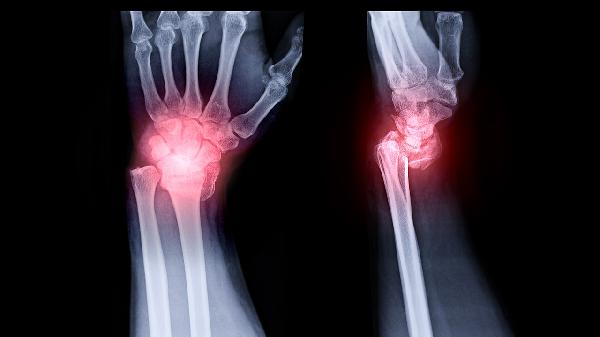

关节炎可通过药物治疗、物理治疗、生活方式调整等方式改善,常用药物包括塞来昔布胶囊、双氯芬酸钠缓释片、硫酸氨基葡萄糖胶囊、甲氨蝶呤片、泼尼松片等。关节炎可能与关节退行性变、自身免疫反应、感染等因素有关,通常表现为关节疼痛、肿胀、活动受限等症状。

关节镜清理术适用于半月板损伤或游离体导致的机械性症状。截骨矫形术通过改变力线分布缓解单侧膝关节磨损。人工关节置换是终末期病变的有效手段,髋关节置换后10年生存率较高。软骨移植术适合局限性软骨缺损的年轻患者。关节融合术多用于踝关节或腕关节严重破坏的病例。